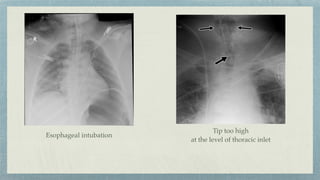

Esophageal intubation- Right posterior oblique view

Esophageal intubation

Tip too high

at the level of thoracic inlet